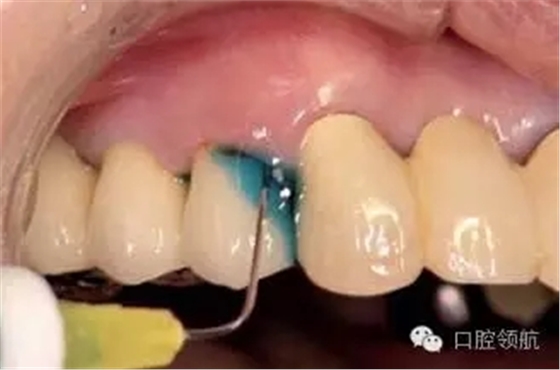

現(xiàn)在的牙周治療方法,是以機(jī)械性治療中加入抗生素等化學(xué)療法形成的機(jī)械化學(xué)治療為中心的方式。近年來(lái),抗菌性的光線力學(xué)治療法(a-PDT)逐漸被關(guān)注(圖3、圖4)。a-PDT是指感光性藥物在特殊光線的照射下被激活而產(chǎn)生出活性氧的方法。不僅對(duì)細(xì)菌而且對(duì)病毒以及真菌也是有效的,同時(shí)具有無(wú)耐藥細(xì)菌的出現(xiàn)和過(guò)敏等副作用的優(yōu)點(diǎn)。本病例在對(duì)患者進(jìn)行了充分地說(shuō)明,并得到同意后,實(shí)施a-PDT治療1周,患者的不適感消失了(圖5)。

圖3 填入含有0.01% 亞甲藍(lán)光敏催化劑。